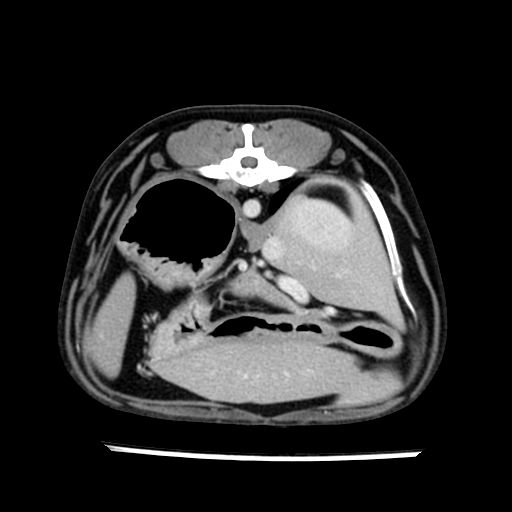

prescritto esame TAC

sequenza immagini limitata al fegato reni e surreni

sospetto adenoma ipofisario vs. meno probabilmente meningioma della base; intertiziopatia polmonare; lesione espansiva epatica, verosimilmente del lobo laterale sinistro, di sospetta natura neoplastica; lesioni spleniche di natura da definire; iperplasia/ipertrofia delle ghiandole surrenali, bilateralmente; vertebra di transizione del rachide toracico; tenosinovite cronica del muscolo bicipite brachiale di destra.